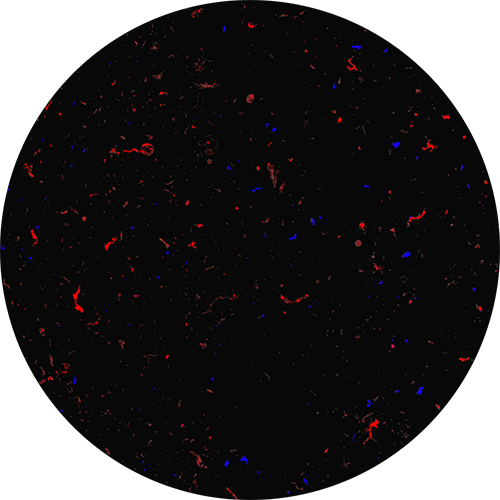

wu應力AAV2樣品中的衣殼聚集

在來自Aura的組合明場(非蛋白質,藍色)和熒光(蛋白質,紅色)圖像中,未受應力的AAV2樣品的庫存中沒有衣殼聚集現象。